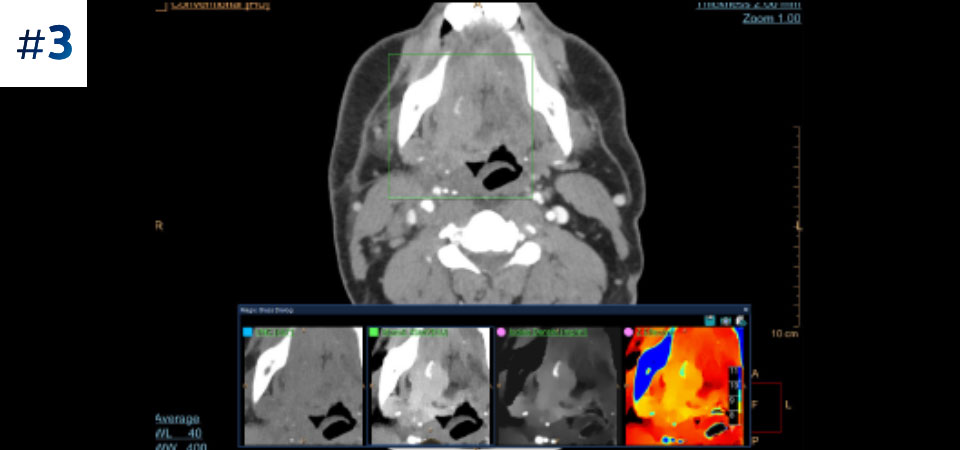

Massa nel collo

Vai oltre la TC convenzionale. Scopri come i risultati con diversi strati del detettore spettrale possono migliorare l'affidabilità diagnostica.

Osserva la differenza tra la TC basata su detettore spettrale e la TC convenzionale